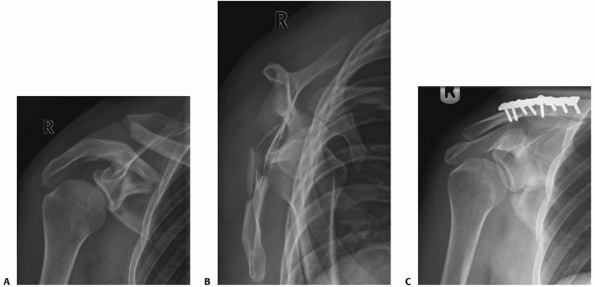

FIGURE 37-8 The radiograph (A) and CT (B,C)

scan of an 80-year-old woman with a posterocranial glenohumeral luxation with a symptomatic pseudarthrosis of an acromion fracture. D. The patient underwent a plate osteosynthesis with bone graft and a reversed shoulder prosthesis. |